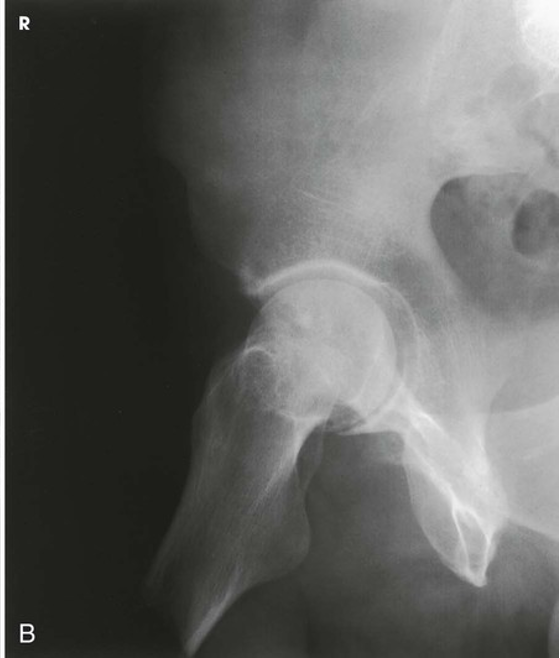

AP Oblique Projection; Acetabulum; Judet Method; RPO and LPO Positions (CR & SS)

External oblique - Perpendicular to the IR and entering at the pubic symphysis

The external oblique is used for a patient with a suspected fracture of the ilioischial column (posterior) and the anterior rim of the acetabulum

The resulting image shows the acetabular rim

(Note: Both images are performed to demonstrate the entire acetabulum as well as the iliopubic and ilioischial columns of the affected side)

POSITIONING: AP Oblique Projection; Acetabulum; Judet Method; RPO and LPO Positions (External Oblique for Right Hip)

AP Oblique Projection; Acetabulum; Judet Method; RPO and LPO Positions (Eval Criteria)

• Evidence of proper collimation

• Acetabulum centered to the IR

• The ilioischial column and the anterior rim of the acetabulum on the external oblique

• Soft tissue and bony trabecular detail

AP Oblique Projection; Acetabulum; Judet Method; RPO and LPO Positions (External)